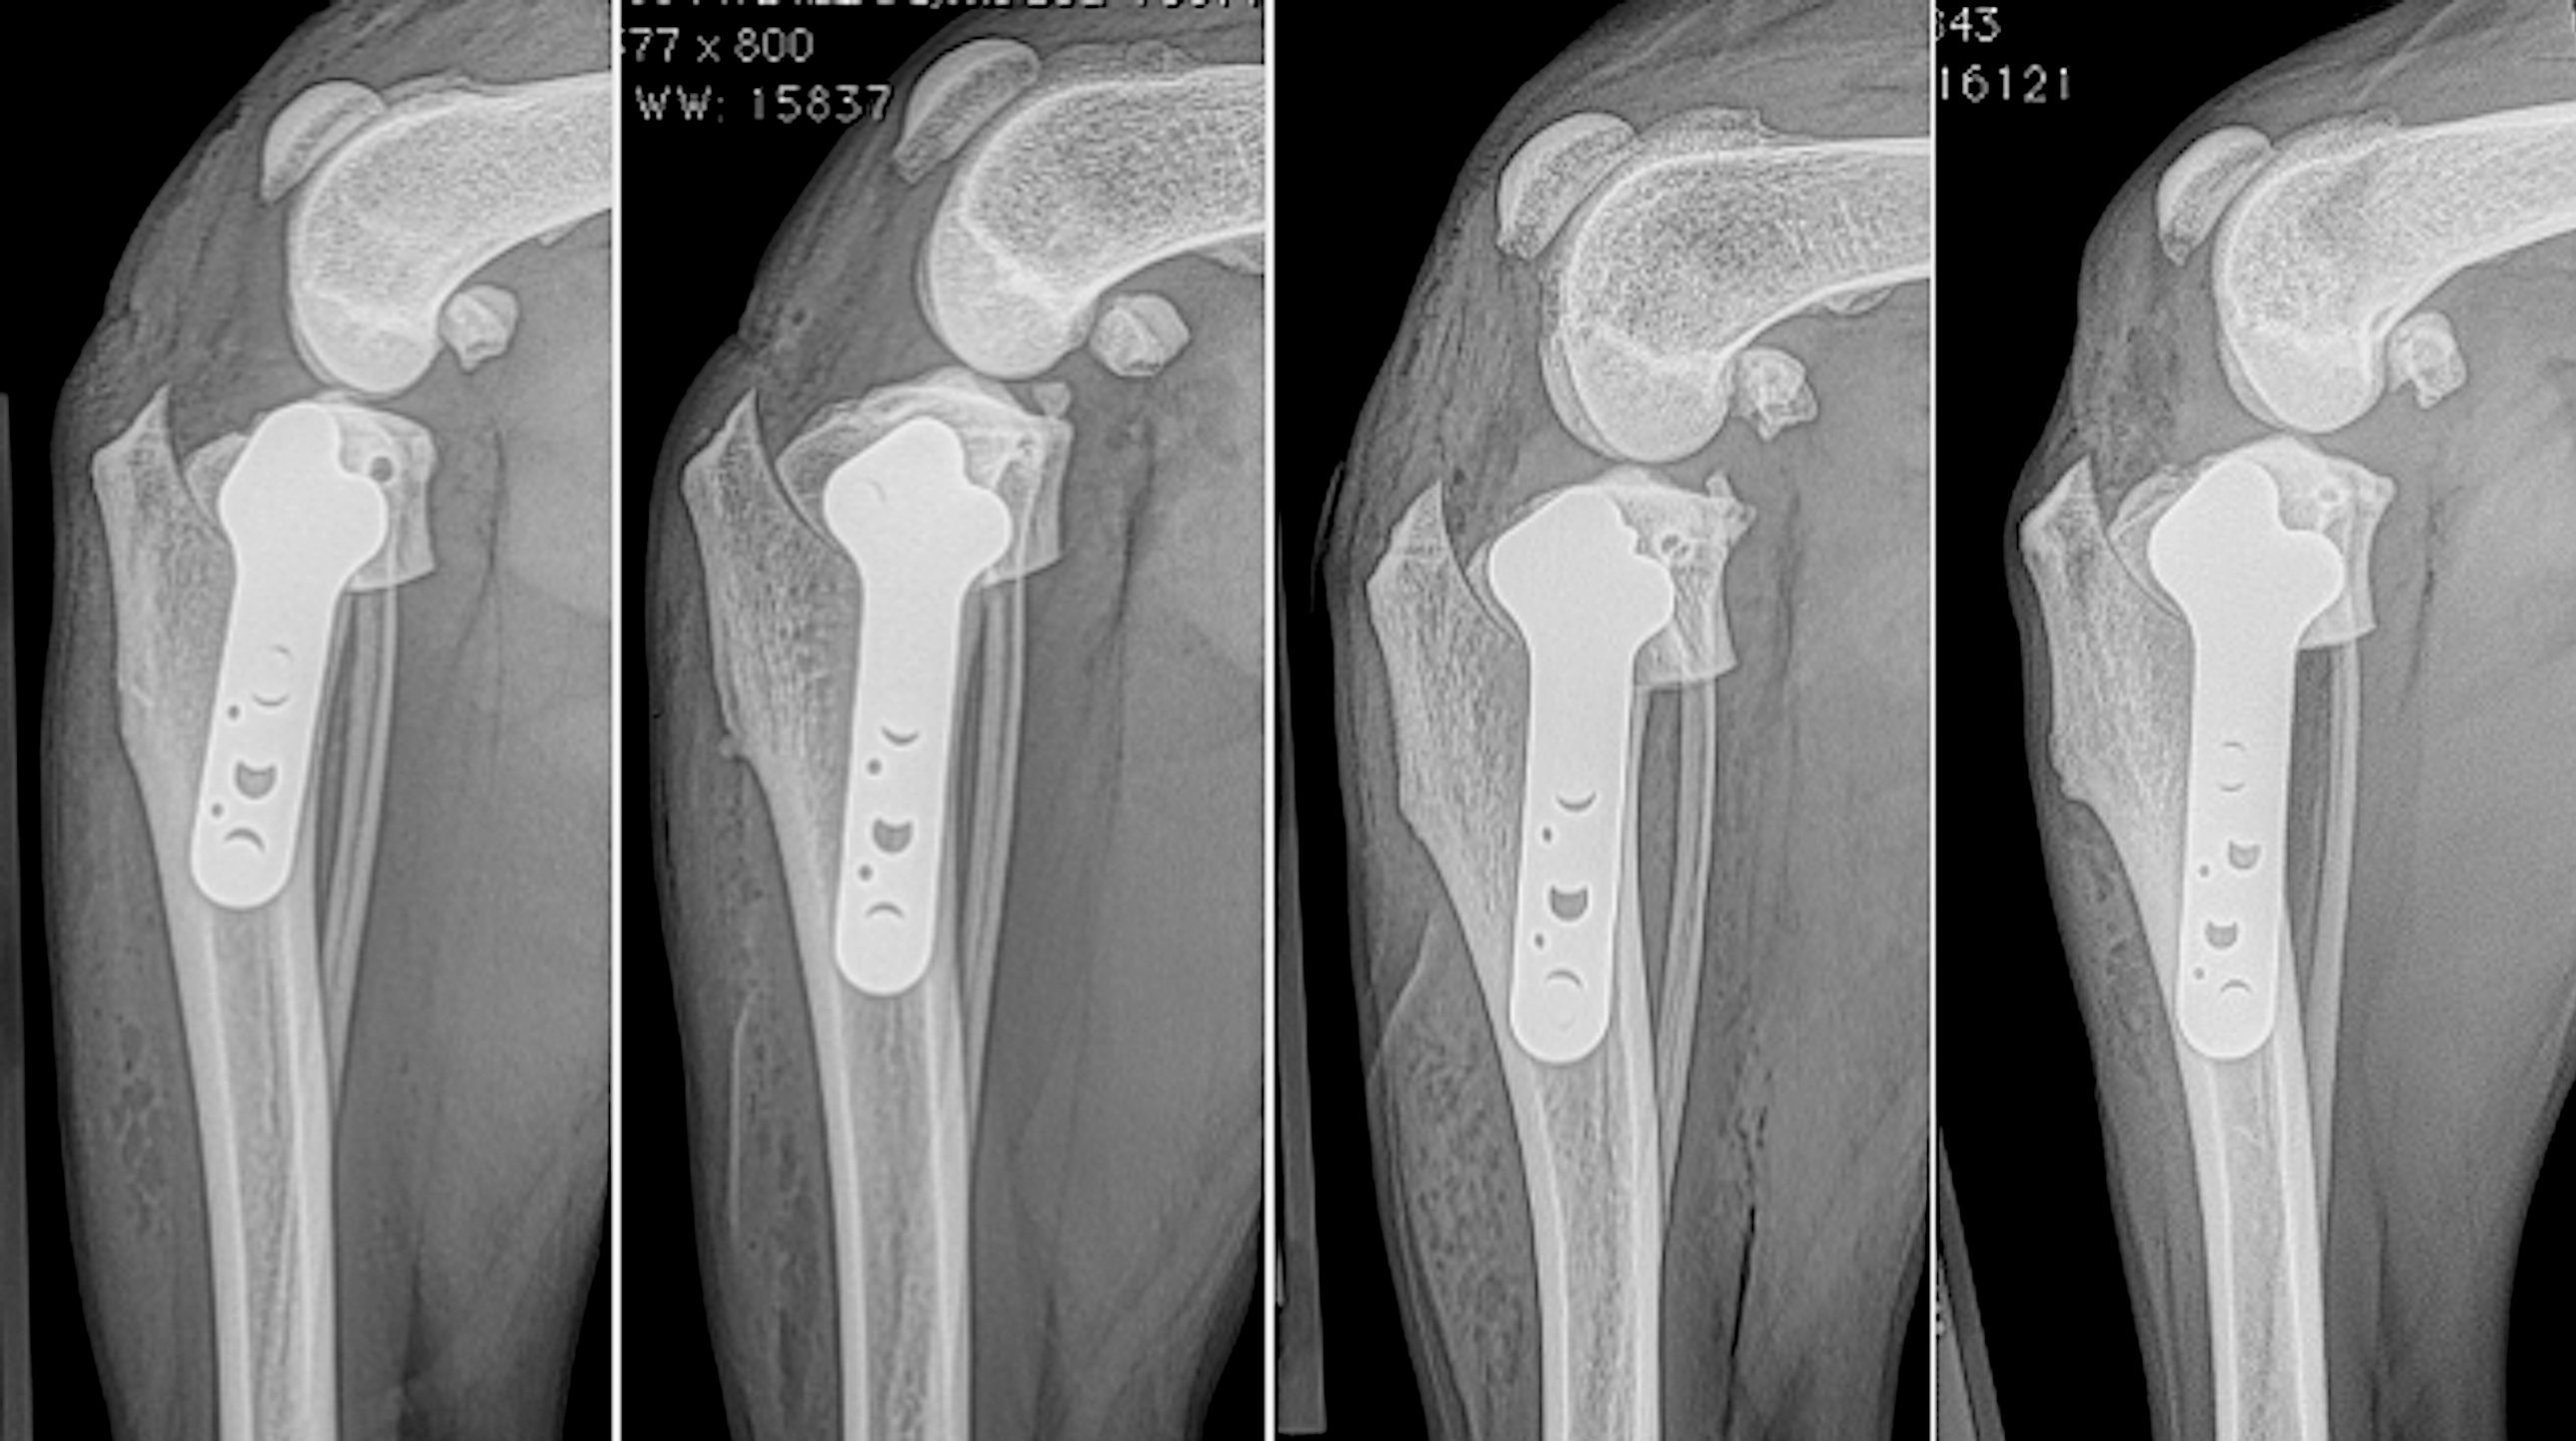

Total Hip Replacement

A CT scan allows surgeons to view bones and joints in 3 dimensions and has many advantages when compared to standard radiographs. A CT may also be used to create life-sized anatomic bone models, custom surgical guides and implants including bone plates or joint replacement components using 3-D printing technology.

3D computerized planning

means surgical precision!

Three-Dimensional Printed Patient Specific Guides for Acute Correction of Deformities